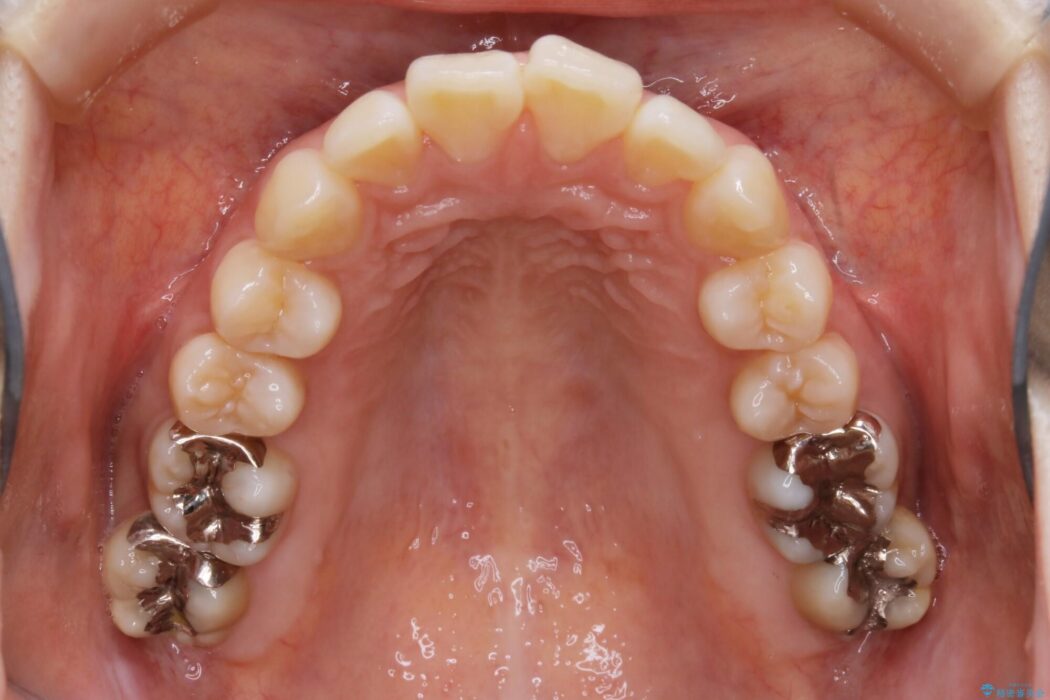

よって患者様ご希望の非抜歯かつマウスピースでの矯正を行うために、最大量の臼歯の遠心移動をして歯列全体を奥へ引っ込める計画をご提案しました。

非抜歯での矯正治療

マウスピースにマイクロインプラントという補助装置を併用することで抜歯をせずとも歯列を整えるスペースを確保することができます。奥歯から順に移動させていくので前歯に変化が出るまでには時間がかかってしまいますが、健康な歯を抜歯することなく理想的な歯並びを手に入れることができます。